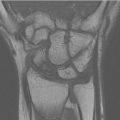

Triangular fibrocartilage complex tear

Cause of ulnar sided pain.

Triangular fibrocartilage disc is T2 hypointense (black).

Two distal attachments to ulna—fovial and styloid; can have some T2 grayish signal normally due to fibrovascularity.

T2 hyperintense fluid signal to diagnose tear (► Fig. 4.4).